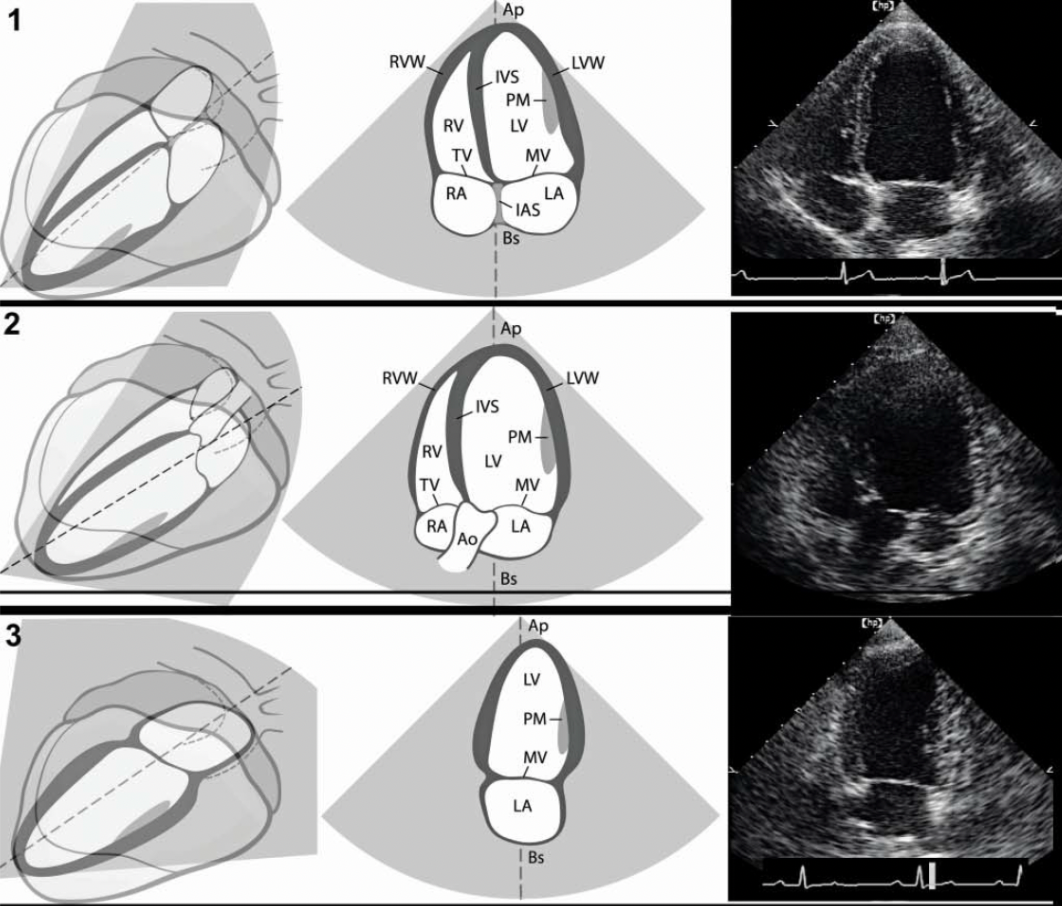

Name the ECHO VIEW and STRUCTURES

LPS LONG AXIS